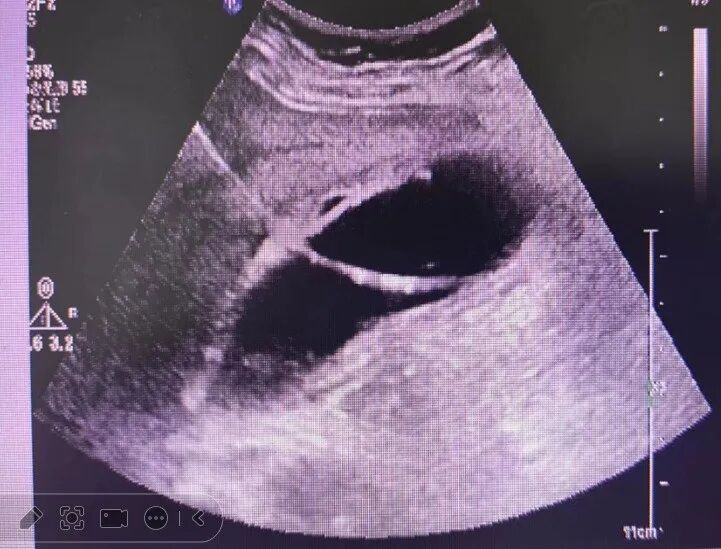

超声引导下经皮经肝胆囊穿刺置管引流术(PTGD)是一种在超声影像技术引导下,通过经皮、经肝途径对胆囊进行穿刺,并置入引流管以达到引流胆汁、缓解胆囊压力和治疗相关疾病的介入性操作。在实时超声图像的监视下,确定胆囊的位置、大小和形态。选择合适的穿刺点和进针路径,使用穿刺针穿过肝脏组织进入胆囊,然后置入引流管,使胆汁能够顺利引出体外。PTGD 作为一种微创治疗方法,在缓解胆囊炎症、降低胆囊压力、改善患者症状等方面具有显著效果。尤其对于高危患者,可作为手术前的过渡治疗,降低手术风险,提高手术成功率。该技术适用于:

2.超声定位

- 消毒皮肤后,涂抹耦合剂,使用超声探头再次确定胆囊的位置、穿刺点和进针路径。

- 在超声实时引导下,将穿刺针沿预定的进针路径缓慢刺入肝脏,然后进入胆囊。

- 当针尖进入胆囊腔后,拔出针芯,如有胆汁流出,证实穿刺成功。

- 通过穿刺针置入导丝,退出穿刺针,沿导丝置入引流管。

该患者为老年女性,进食后伴有上腹部不适,无明显恶心、呕吐,未予特殊处理,后期伴有发热,体温达38℃以上,对症处理后体温可有所下降,进食伴有右上腹明显疼痛感,导致无法进食,发病1周后就诊,完善相关检查后确定为胆囊结石伴急性胆囊炎,胆囊周围渗出明显,综合考虑患者病史较长、高龄、胆囊周围炎症重,直接行腹腔镜胆囊切除术处理增加胆道损伤风险,故综合评估后给予治疗计划如下:

该患者及家属同意相关治疗方案并遵照医嘱执行,7分钟顺利完成胆囊穿刺置管处理,术后体温恢复正常,次日恢复正常进食。术后引流管内引流液体为脓性,后期为正常胆汁。